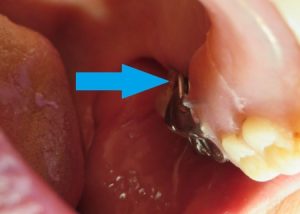

HOME > 歯科ブログ > ・80代女性 金属バネが折れた部分入れ歯を修理して安定して使用できるようにした症例写真 > itosika_No29_after_002 itosika_No29_after_002 投稿日 2025年7月17日